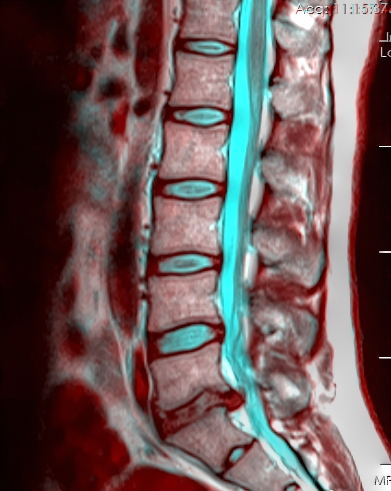

This Cochrane review of the diagnostic accuracy of red flags for fracture or malignancy in patients with low back pain in multiple settings found that corticosteroid use (+LR 4-48.5), severe trauma (+LR 3.4-10), presence of overlying contusion (+LR 31.1, single study), or history of cancer (+LR 15.3-35) had the highest diagnostic utility in predicting need for imaging. However, the overwhelming heterogeneity in setting, design and results of the 14 studies analyzed precluded pooling and suggests that these likelihood ratios should be interpreted with a great deal of caution. Future research is needed to look at the sensitivity & specificity of combining multiple red flags for ED patients with low back pain in order to be clinically useful.